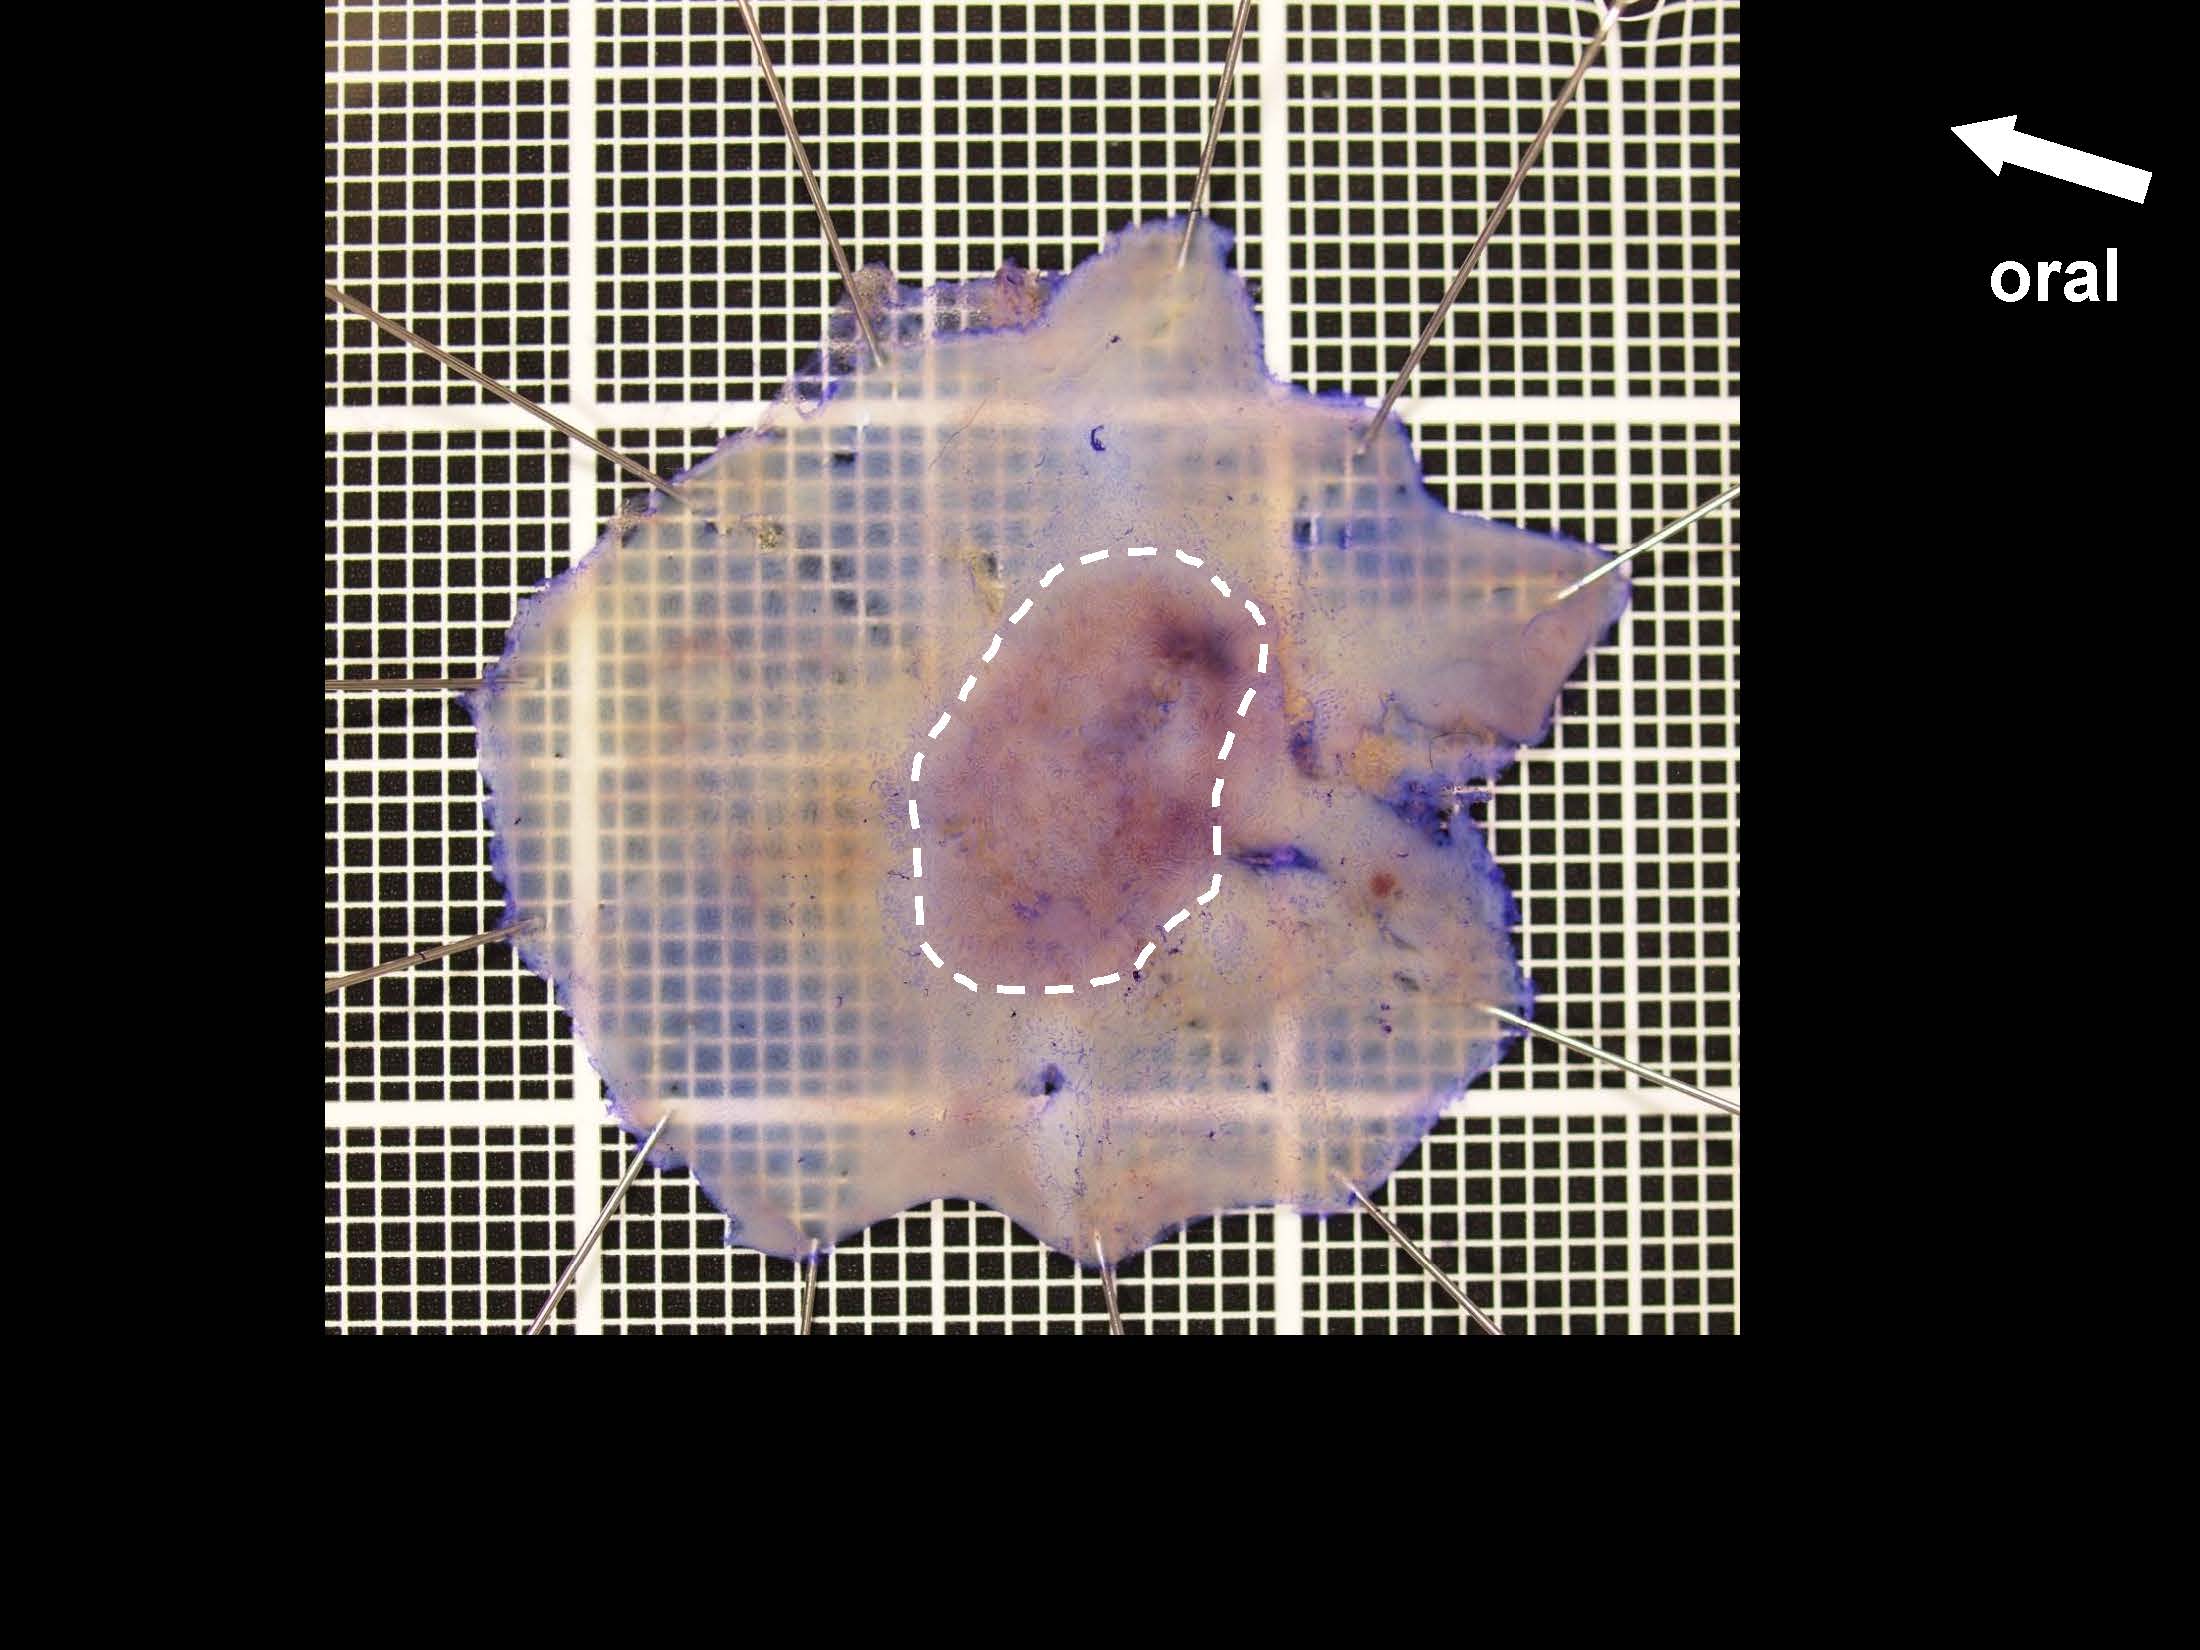

内視鏡検査・治療

消化管Mapping

消化管Mapping~大腸~

消化管Mapping~大腸~ 2021.10.27